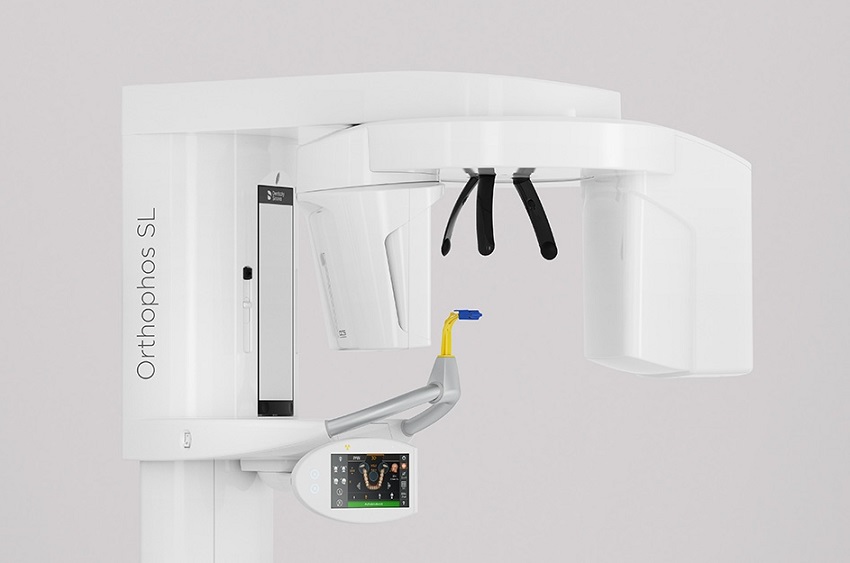

- 3D dijagnostika - digitalni ortopan

- Radiologija

- Orthophos SL 3D